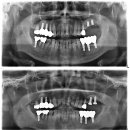

가장 정석적인 치료를 한다면 잇몸을 깨끗하게 관리하면서 교정을 하고 치아가 상실된 부위에 임플란트 또는 브릿지 치료를 하는 것입니다. 하지만 환자분께서는 교정치료를 하실 수 없는 상황이었고, 최소한의 보철로 최대한의 효과를 낼 수 있도록 치료 계획을 세웠습니다. 1. 먼저 심하게 흔들리는 앞니는 발치...

라고 후기를 남겨 주셨습니다. 보통 많은 분들이 얼굴을 올려도 된다고 말씀해 주시지만, 큰 변화가 있는 입 주변만 올렸는데요. 이번 포스팅의 주인공 사진을...네비게이션 임플란트 활용(짧은 기간, 최소 개수) 안녕하세요. 치과의사 민재홍입니다. 이번 포스팅은 심한 잇몸 염증(치주염)으로 인해 다수의 발치...

Dentistry, Combination ART & SCIENCE(2025-07-01 16:56:00)